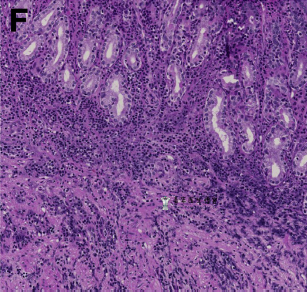

内镜下活检后,组织病理学提示粘膜和粘膜下层中性粒细胞广泛浸润(图E,F)。